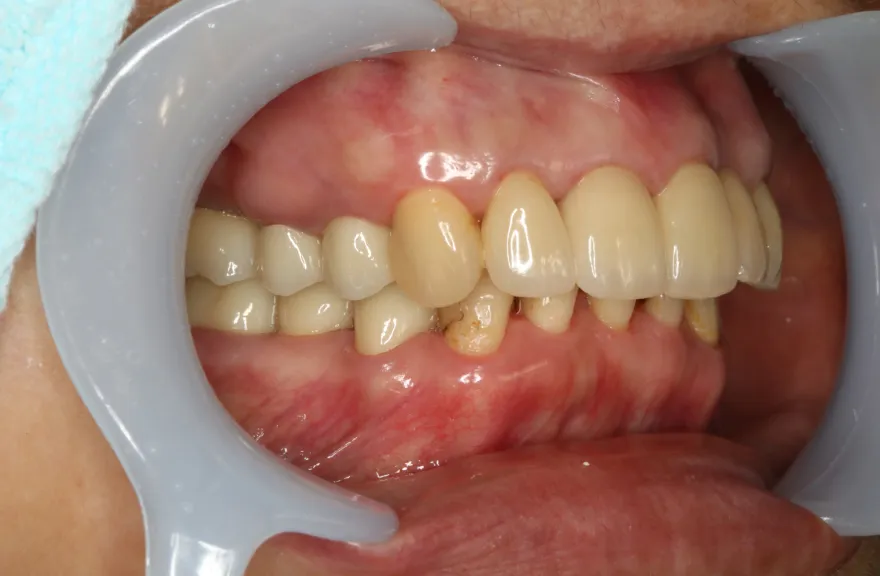

【治療例 3】奥歯が痛い、全体的にみて欲しい 60歳

- 相談内容

-

今まで何回歯を入れてもトラブルが起きるために、奥の歯を入れないまま今日に至る、ということでした。

噛み合わせ・骨格を読み解き、今後の人生でトラブルが起きにくいように全体的な治療計画を練りました。 - 治療費用・方針

骨格の前後的な差がある方でした。術前のレントゲンより、上下で歯牙の損傷に明らかな差があるのがみてとれます。

上の歯がないところにインプラント治療を行い、上顎は全てインプラントフィクスチャーによる固定性の歯を入れられることも費用的には可能な方でした。

しかし、治療において重要なのは今目の前の歯を見ることではなく、なぜ目の前の歯になったかを考え、未来へ活かすことです。

骨格的な前後差を考慮することなく歯をいれても、装着した人工物は決して長持ちしません。

今回の症例では、敢えて上顎は総義歯形態をとり、骨格的な前後の差を解消するよう工夫しました。

上顎の残っていた歯も、差し歯としては使えずとも、敢えて根だけ残すことによって組織を温存し、義歯の安定に寄与するよう設計しました。

ここまで全体的にしっかり治療しておけば、今後の人生においてトラブルになるようなことにはならないでしょう。 - 治療のリスク